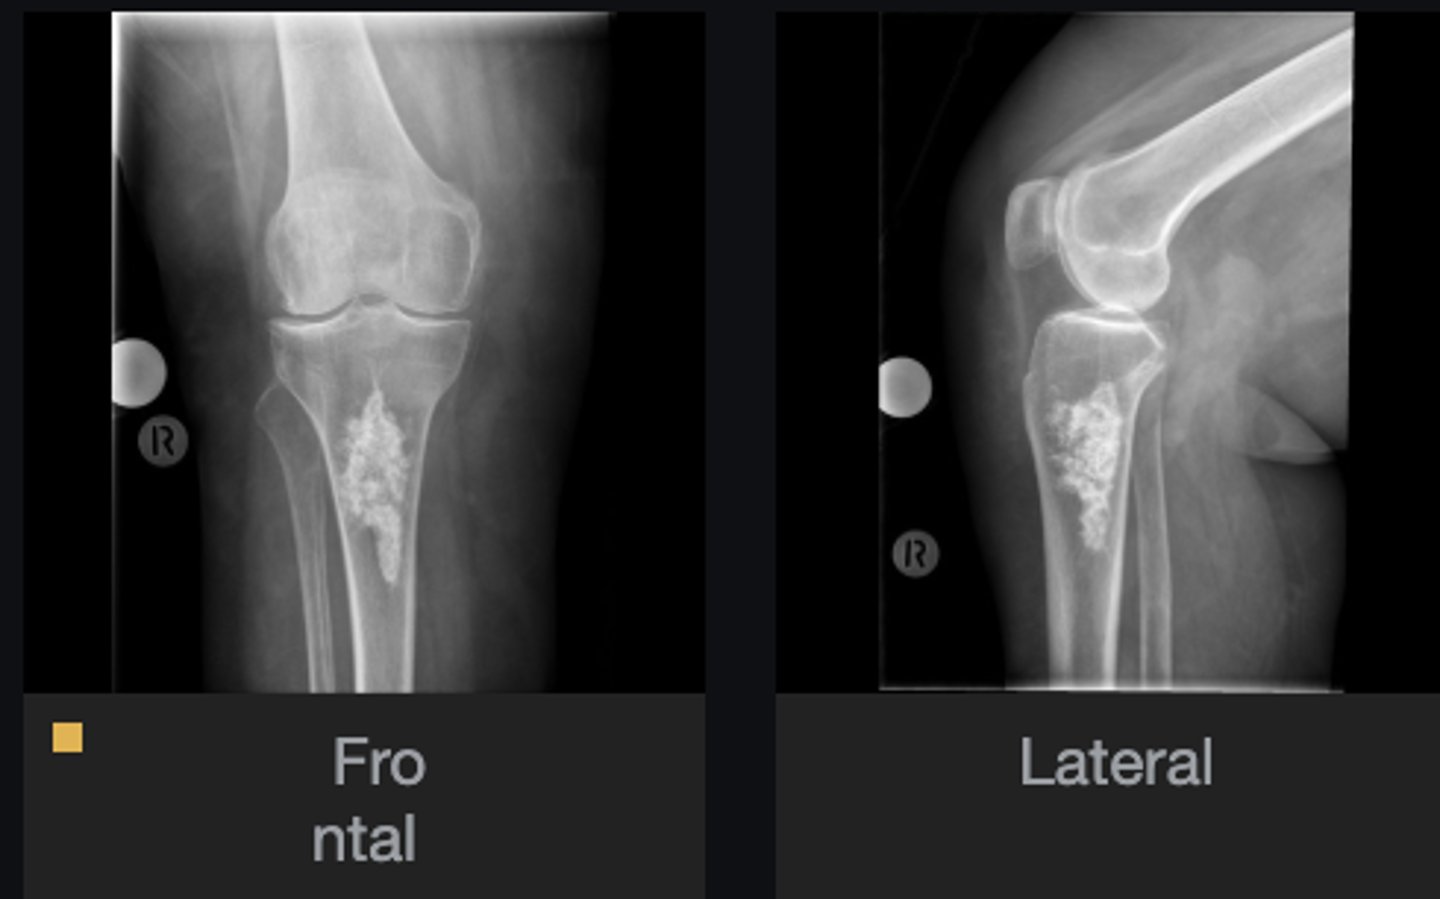

- Flocculent calcification

- Metaphysis/diaphysis

- Enchondroma

- Cartilaginous matrix

Describe the lesion

<p>Describe the lesion</p>

Enchondroma

Most likely diagnosis?

<p>Most likely diagnosis?</p>

Malignant transformation (rare)

Concerns/complications?

<p>Concerns/complications?</p>

Refer to orthopedist

Next step?

<p>Next step?</p>